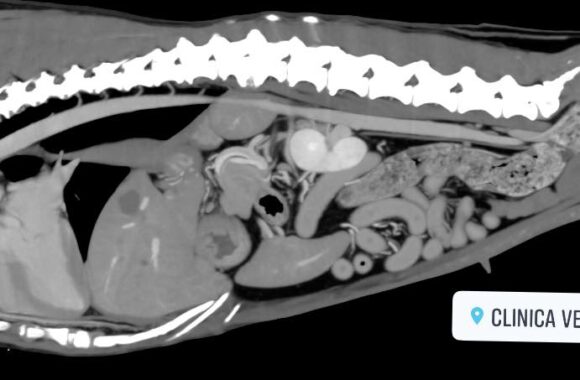

Il Servizio Tac Veterinaria a Portici

Attualmente l’unica clinica veterinaria di Napoli e provincia che ha a disposizione una TAC Multistrato da 128 strati in struttura, ultra veloce (total body in meno di 15 sec.), con refertazione in 24h/48h.